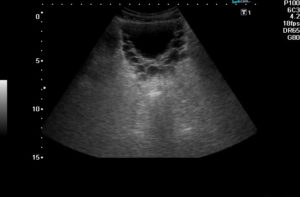

Если диагностика проводится трансабдоминально, то пациент ложится на кушетку с освобожденным от одежды животом. Врач водит ультразвуковым датчиком по кожному покрову, сканируя мочевой пузырь и близрасполагающиеся органы.

Для оценивания работы предстательной железы в ходе процедуры врач просит посетить туалет. Далее производится визуализация после опорожнения мочевого пузыря. Обычно процедура не занимает более 20 минут. При трансректальном УЗИ ультразвуковой зонд вводится в прямую кишку.

- Трансабдоминальное исследование. Делают в положении лежа на спине, диагностику осуществляют через брюшную стенку. Условие проведения исследования — наполненность мочевого пузыря. Абдоминальное УЗИ позволяет определить объем, размер, строение органа. Применяют у мужчин и женщин.

Наиболее распространен трансабдоминальный метод осуществления исследования.

В первую очередь пациент ложится на кушетку. После освобождения низа живота от одежды следует процедура нанесения специального геля. Затем врачом прикладывается датчик на область, куда нанесен гель, и при оказании небольшого давления водится по животу для рассмотрения мочевого пузыря и органов, находящихся в непосредственной близости.

Длительность исследования составляет примерно 20 минут. После этого пациенту передается бланк с указанием итогов процедуры.

Прежде всего от пациента требуется соблюдение не сложных подготовительных мер, в частности необходимо убедиться в наполненности органа. Врач ультразвуковой диагностики проводит исследование трансабдоминальным путем.

Во время сеанса пациент лежит на кушетке в положении на спине (иногда требуются дополнительные измерения в положении на боку).

На датчик и обследуемую область наносят специальный гель, который улучшает проведение ультразвуковых волн и одновременно обеспечивает скольжение датчика. Средство гипоаллергенно, не имеет цвета и запаха, легко смывается с поверхности не оставляя следов.

Врач проводит осмотр и определенные замеры согласно протоколу, затем просит обследуемого сходить в туалет и повторно осуществляет манипуляцию, обследуя уже опустошенный орган.

Общее время процедуры — 10-20 минут. Часто пациенту назначают комплексное обследование включающее оценку состояния мочеточников и почек.

Теперь пациента будет интересовать вопрос о том: “Как делают УЗИ мочевого пузыря?”.

- Трансабдоминальное УЗИ выполняется предельно просто: пациент приходит в кабинет УЗИ и врач просит его лечь на кушетку и оголить живот. Затем на область исследования наносится специальный гель, который необходим для улучшения его скольжения по коже и повышении качества исследования, ведь воздух, который скапливается между трансдьюсером (датчиком) и кожей является довольно сильным искажающим элементом. Из-за него может сильно снизится точность и достоверность получаемых данных. После окончания исследования, пациент может сходить в туалет и убрать остатки геля при помощи полотенца или салфеток.